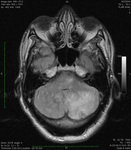

Lesão de massa grande no cerebelo com efeitos de pressão, conforme observado na ressonância nuclear magnética (RNM)

Do acervo de Dr. S. H. Subramony; usado com permissão